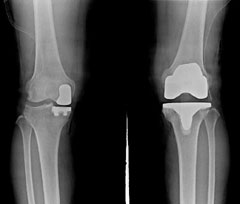

무릎 관절 반 치환술(왼쪽)과 전 치환술.

로봇으로 손상된 무릎 관절의 일부만 인공관절로 교체하는 '로봇 인공관절 반(半) 치환술'이 국내 연구팀에 의해 개발됐다. '반 치환술'은 관절 전체를 교체하는 '전(全) 치환술'에 비해 수술이 까다롭고, 실패율이 높아 지금까진 관절 일부가 손상된 환자도 안전한 '전 치환술'을 받는 경우가 많았다.